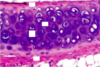

___________ is a dense CT interface around hyaline and elastic cartilage that carries the blood supply for avascular cartilage and is the source of new cartilage cells

Perichondrium

Inner chondrogenic layer

What part of hyaline cartilage surrounds the isogenous cell group and contains high amounts of GAGs and lower amounts of collagen?

Territorial matrix

What part of hyaline cartilage surrounds the territorial matrix and contains more collagen II and fewer proteoglycans?

Interterritorial matrix